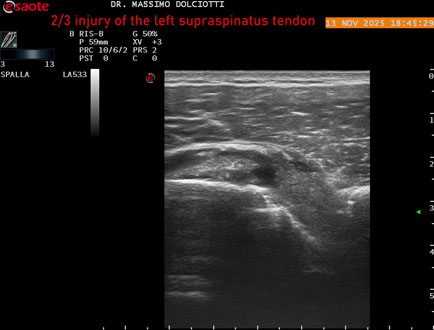

Età Paziente: M 58 anni

Motivazione dell'esame: da 4-5 mesi dolore alla spalla sinistra.

Commento all'esame: le immagini ed il video documentano il tendine sovraspinato sinistro disomogeneo per evidenza, in sede mediale sottobursale, di area ipoecogena di 4,5 mm per uno spessore di 3,3 mm, da ricondurre a lesione parziale che interessa i 2/3 del tendine.

Conclusioni: lesione 2/3 del tendine sovraspinato sinistro (2/3 injury of the left supraspinatus tendon).

Presentazione: Dr. Massimo Dolciotti - Ancona

Elaborazione digitale: Andrea Dini - Ancona